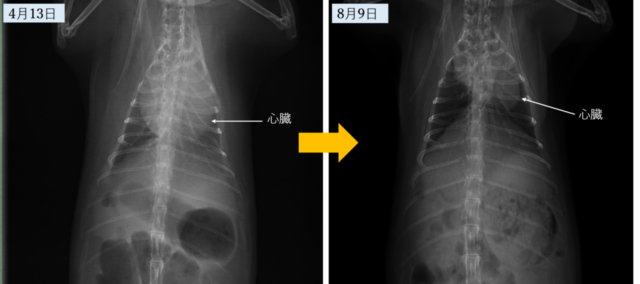

③心臓肥大

と、大きく3つも悪いところがあり、危険な状態で、このまま急変もあり得るとの診断でした。

検査の結果、心嚢水のため大きくふくれていた心臓が小さくなり肺に溜まった胸水もなくなっているとのこと

体重も1kgこえて「本当に頑張りましたね」と言っていただき診察中にも関わらず涙があふれて止めることが出来ませんでした

院長先生からも「今後は薬も酸素室も不要」とお墨付きをいただき病気する前と変わらず生活ができるようになりました